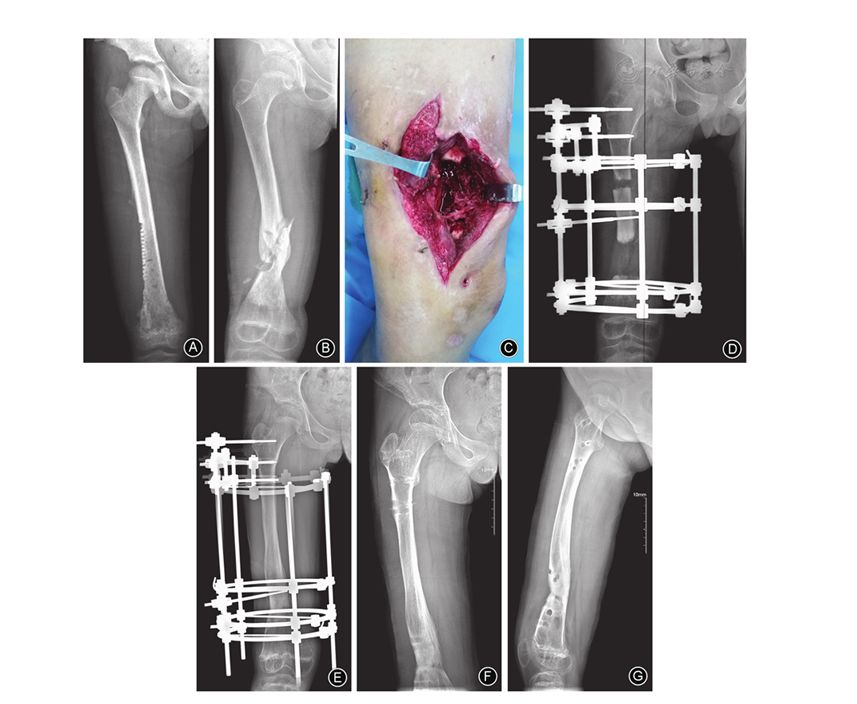

图1 女,9岁,右大腿远端肿痛、局部皮温升高2个月 A 术前股骨正位X线片示右股骨骨髓炎 B 行右股骨钻孔、置管冲洗引流1个月,股骨正位X线片示股骨中下段病理性骨折 C 行清创、死骨清除并植骨 D Ilizarov外固定架固定术后股骨正位X线片示骨缺损约13.5 cm E 术后18.5个月,股骨正位X线片示骨折断端愈合良好,延长骨段矿化完全 F,G 拆除外固定架后2个月,股骨正、侧位X线片示骨搬移断端对合良好,骨性愈合

术后每2周摄患肢正、侧位X线片,无一例发生骨化不良及提早骨化。本组31例患者中,28例骨断端一期经外固定持续轴向加压后骨性愈合(图1,图2);2例股骨、1例胫骨断端经二期植入髂骨松质骨、轴向加压后实现骨性愈合。骨愈合时间6~18.5个月,平均11.5个月,其中股骨愈合时间(12.59±5.40)个月,胫骨愈合时间(10.30±1.87)个月,两组比较差异无统计学意义(t=1.60,P=0.13)。